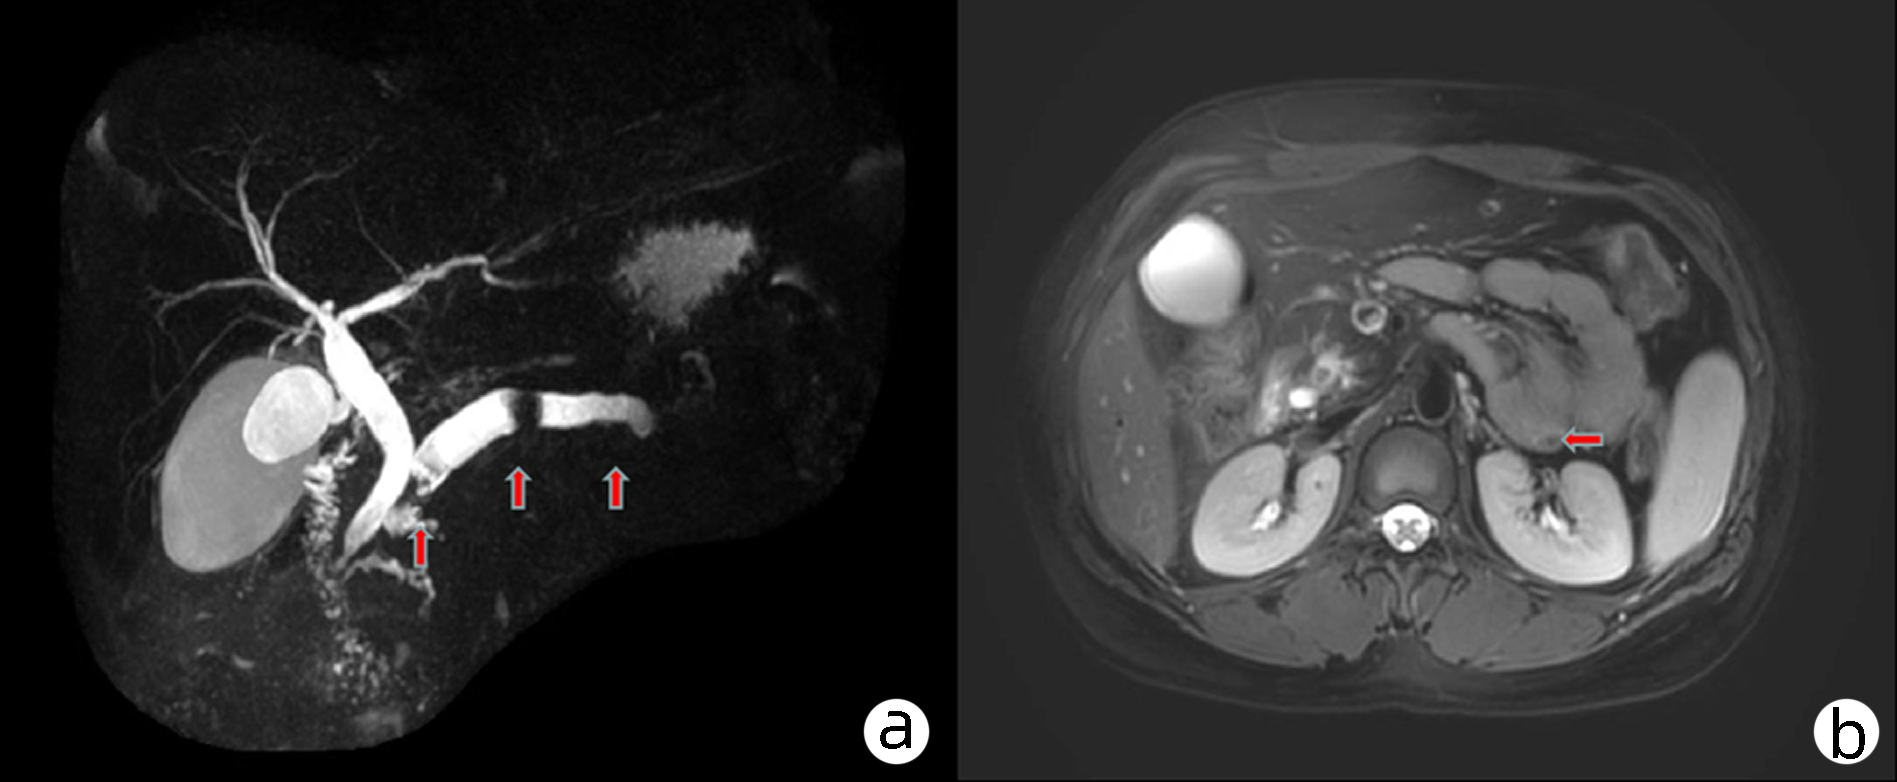

Chronic pancreatitis and pancreatic duct stones with ectopic pancreas in the jejunum: A case report

Xiaokang YI, Ping TIAN, Qiuxi LI, Xuebin LIAO, Jian WEN

2023, 39(8): 1919-1921. DOI: 10.3969/j.issn.1001-5256.2023.08.022

Abstract(809) HTML (416) PDF (2002KB)(94)

Abstract:

This article reports a case of chronic pancreatitis and pancreatic duct stones with ectopic pancreas in the jejunum and discusses its features and impact, including the possible impact of misdiagnosis. Since it was unable to identify the nature of the space-occupying lesion in the jejunum, resection was performed for the part of the jejunum with such lesion.